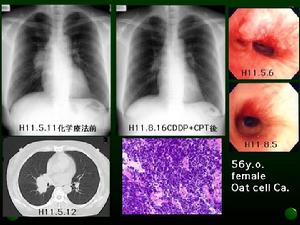

社會獲得性肺炎其表現特徵,結合病理基礎分述如下:

(1)肺紋理增強:此征常見於支氣管肺炎。病毒性感染所引起的肺紋理增強往往比細菌性感染更明顯。這是病原體經支氣管感染和沿支氣管蔓延所引起的X線表現,在病理上從氣管至終末細支氣管以至呼吸性支氣管均可見黏膜有滲出性、增生性或壞死性炎症,以5或6級以下支氣管病變較重,小葉所屬的終末細支氣管及腺泡所屬的呼吸性細支氣管更重,常伴有支氣管周圍肺泡炎,故有人認為肺紋理增強是肺炎的早期X線表現。肺炎所致的肺紋理增強多為普遍性,紋理邊緣比較模糊,藉此可與血管性紋理增強相鑑別。

(2)小結節影:此征多見於腺病毒性肺炎、呼吸道合胞病毒肺炎及麻疹病毒性肺炎等,也可見於細菌性肺炎和真菌性肺炎。病灶直徑多為1~6mm,邊緣比較模糊,以中下肺野為多見。在病理上為終末細支氣管或呼吸性細支氣管周圍炎,也可為腺泡範圍的肺泡炎。前者與普遍性肺紋理增強及肺氣腫並存。多見於病毒感染,後者多與小葉融合病灶並存,可見於病毒感染或細菌性感染。

(3)小斑片狀或斑片狀融合影:此症可見於各種原因所致的支氣管肺炎。在X線上表現為直徑1~2.5cm邊緣模糊的

社會獲得性肺炎(4)肺段及大葉陰影:此種表現多見於肺炎鏈球菌肺炎、肺炎桿菌肺炎、金葡菌肺炎、卡氏囊蟲肺炎及腺病毒肺炎。肺炎鏈球菌肺炎和肺炎桿菌肺炎占據一個肺段或一個肺葉者居多,而卡氏肺孢子蟲、腺病毒肺炎可同時累及幾個肺段或肺葉,可於緻密陰影中見含支氣管影像。在病理大體標本上可見病變為分界清楚的、呈褐紅色或灰白色的實變區、病變體積多不縮小,在顯微鏡下於肺泡腔內可見纖維、紅細胞及白細胞滲出。

(5)條索狀及網狀陰影:此症見於放射性肺炎、慢性肺炎及間質性肺炎,病變以增生為主,多發生於肺泡壁,中葉間隔,也可與實質性肺泡炎混合存在。這種增生病變還可與部分肺萎陷同時存在。慢性肺炎可伴有支氣管擴張,在X線上表現為斑片狀不規則索條狀的混合陰影。邊緣可清楚,也可模糊。一般說來此種病變較滲出性肺泡炎吸收緩慢。

(6)球形陰影:此症見於金葡菌肺炎、真菌性肺炎等,前者在病理上為膿腫,境界模糊或比較清楚。血源性金葡菌肺炎常為多發,在X線上,金葡菌肺炎可表現為多發或單發的球形陰影,直徑多為1~3cm左右,邊緣比較清楚.密度較均勻,但在短時間內可形成空洞。真菌性肺炎所形成的球形陰影的病理基礎是膿腫或肉芽腫。

(7)空洞:主要見於化膿性肺炎及真菌性肺炎,尤以金葡菌肺炎常見。在X線上表現為環形透明區,邊緣比較清楚或模糊,其壁厚薄各不相同,病變與正常肺組織分界不清,空洞內為壞死組織,若引流支氣管因炎症而形成活瓣,由於空洞內含氣量不斷增多,壓力增大,因而使空洞增大,壁變薄,一般稱此症為肺氣囊。這種現象見於金葡菌,A型溶血性鏈球菌等革蘭陽性球菌感染。在X線上表現為薄壁空腔,在肺炎吸取後可短時間內消失,也可殘留數月,在病理上其壁為薄層纖維組織。

(8)肺氣腫:多見於小兒支氣管肺炎,尤以腺病毒肺炎、麻疹肺炎、呼吸道合胞病毒肺炎多見。在X線上表現為胸部增大,肋間變寬,兩肺透明度增高,膈低平,在病理上為全小葉肺氣腫、肺泡腔擴大、肺泡壁變薄,病變常發生在各肺葉的邊緣,如上、中、下葉的前緣。

(9)胸膜病變:肺炎可合併胸膜改變,當發生胸腔積液時,積液的性質可不相同,如漿液性、漿液纖維素性或化膿性。化膿性胸腔積液多合併化膿性肺炎,漿液纖維素性積液複合並於病毒性肺炎。在X線上可見胸腔內有液體,胸膜可見充血、水腫和炎性細胞浸潤。